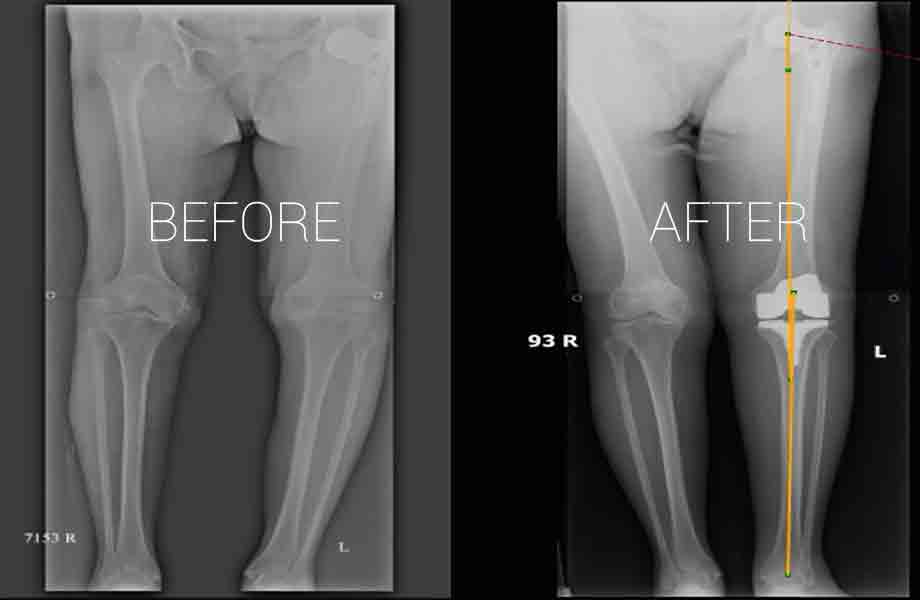

Total Knee Replacement